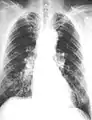

Extensive fibrosis of pleura and lung parenchyma

61-year-old working industrially with asbestos for decades